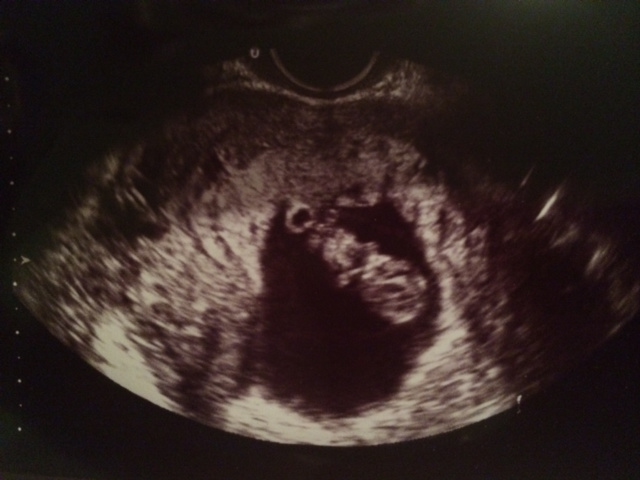

Thanks for checking. I actually had another u/s done vaginally at 9 weeks and now it looks different. I guess now I am confused because you still see the yolk sac, which I thought didn't move and to me this would look like a girl, right?!?!

Thanks for visiting my thread and taking a guess :) Yes, the yolk sac seems to be on the left now, so my guess would be girl now. So confusing! lol I guess we'll have to wait for the nubs and skulls. Keep me updated though, I'm dying to know what you're having. Good luck!